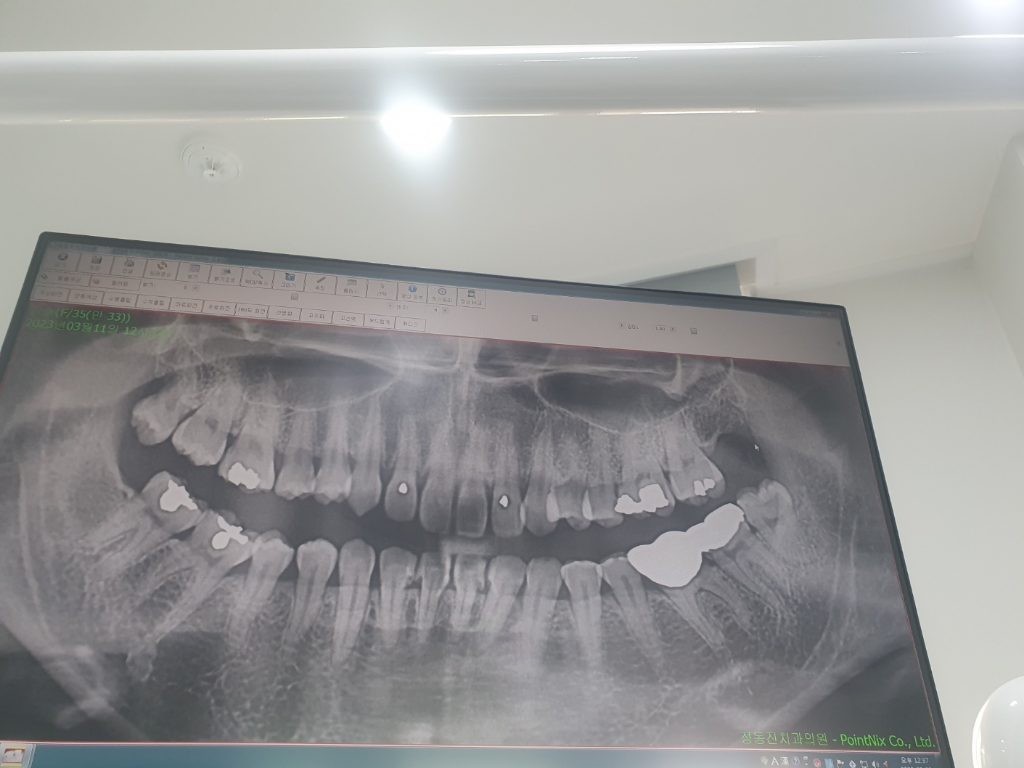

칫솔질 자극시 나타나는 출혈 외 불편한 증상은 충치의 가능성이 있어보입니다. 다만 좀 더 명확한 증상이 드러나거나 방사선 사진상 충치 등이 확인이 된다면 치료가 필요할 수 있습니다.